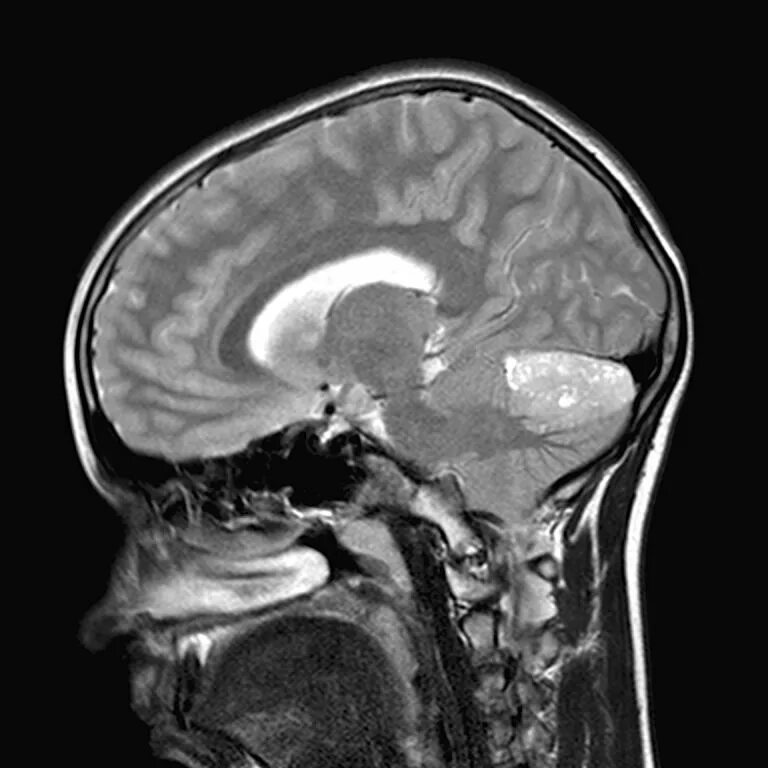

Медуллобластома это